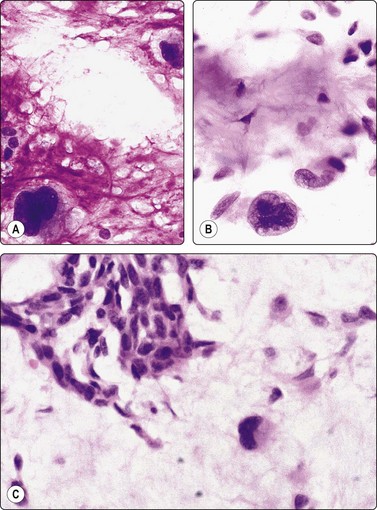

image

Fig. 4.7 Basaloid squamous cell carcinoma of head and neck

(A) Poorly differentiated cells with squamous features (MGG, HP; (B) Tissue section mimicking adenoid cystic carcinoma (H&E, IP).

Basaloid squamous carcinoma (Fig. 4.7) is a rare distinct variant of squamous cell carcinoma of the head and neck, which is clinically aggressive and has a predilection for the hypopharynx and the tongue. The smear findings are of squamous cell carcinoma without specific features, but a predominance of basal cells may make the distinction from the solid variant of adenoid cystic carcinoma difficult.43